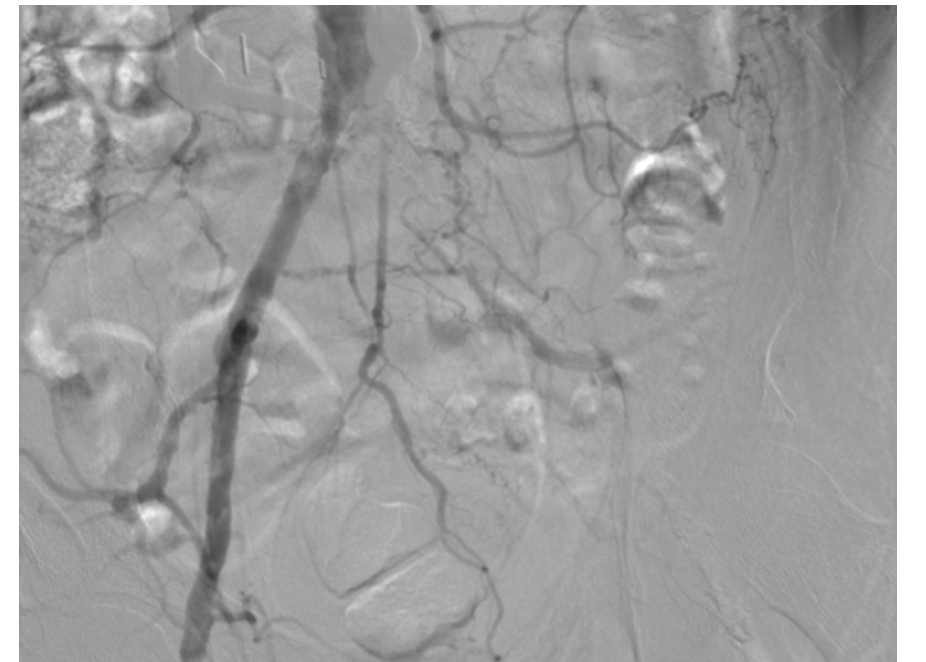

One month after this endovascular procedure, the patient underwent left common femoral endarterectomy with right-to-left femoral-to-femoral bypass grafting (Figure 5 and Figure 6).

This case demonstrates the first in-human experience of transradial IVL for calcific lower-extremity PAD. The length and profile of this new catheter makes it compatible with a transradial approach with excellent efficacy. IVL makes iliac artery intervention safer due to its ability to fracture intimal and medial calcium. This translates into less potential for vascular perforation due to refractory calcific plaque. In our case example, left external iliac artery stenting was unnecessary due to the excellent result achieved with IVL alone. As more endovascular cases are being performed from alternate access sites, IVL is a viable treatment option from these novel approaches.